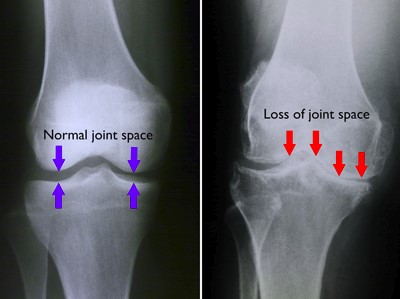

Osteo-Arthritis (OA) simply means “bone joint inflammation”. It is the most common chronic joint problem. OA occurs when the cartilage between joints breaks down leading to trauma and bone damage. On X-rays – you can see a visible narrowing or sometimes even absence of space between the joint surfaces.

In OA – the clinical symptoms start slowly. At first – patients will have minimal symptoms. As their condition worsens – they begin to experience joint stiffness and then, pain, swelling, joint failure and immobility16.